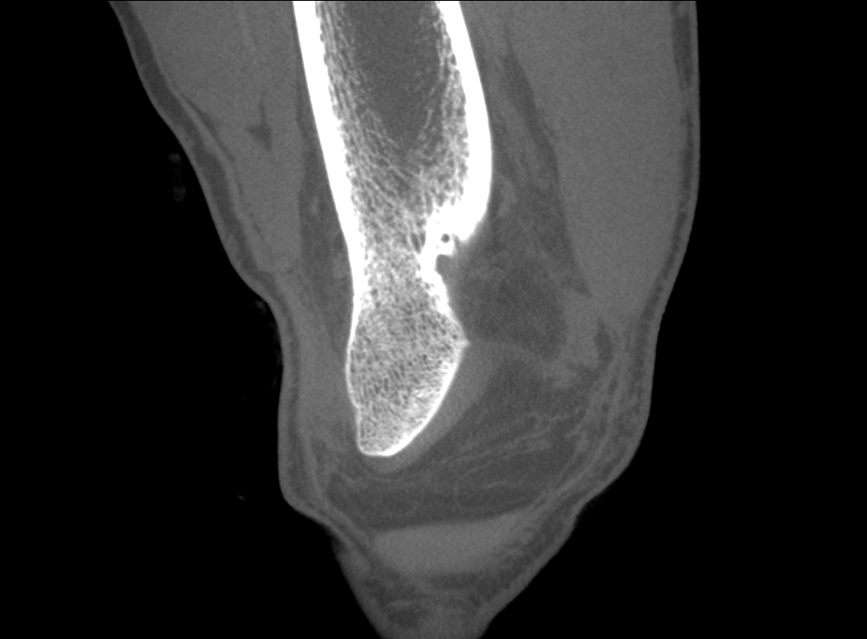

HRCT

High Resolution Computed Tomography. Outstanding image quality with a voxel size up to 100 µm